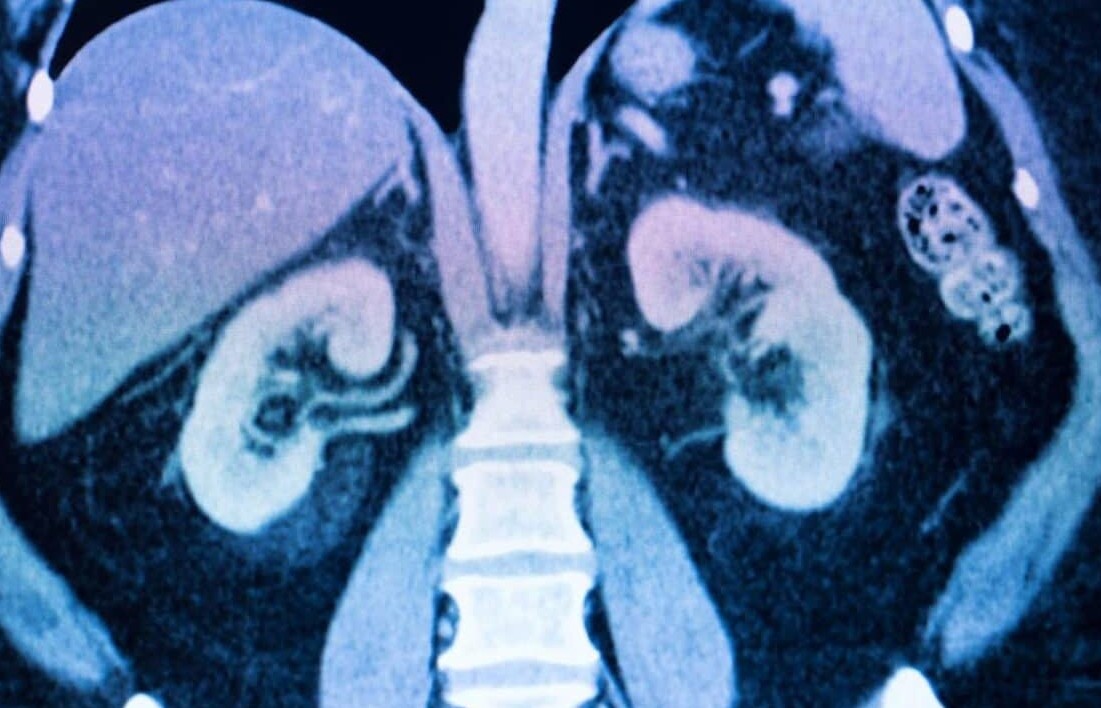

Μια νέα μελέτη που δημοσιεύθηκε στο Communications Biology αναδεικνύει πώς τα μικροπλαστικά, ιδίως αυτά που βρίσκονται στο εμφιαλωμένο νερό, βλάπτουν τα ανθρώπινα όργανα, ιδίως τα νεφρά.

Το Benzo[a]pyrene (BaP) είναι μια άκρως τοξική ουσία που ταξιδεύει με τα εν λόγω σωματίδια εντός του οργανισμού μας και απορροφάται κυρίως μέσω του πεπτικού συστήματος. Η έκθεση αυτή σε τέτοιες ουσίες οδηγεί σε συστηματική φλεγμονή και προκαλεί βλάβες σε όργανα όπως τα νεφρά, επιβεβαιώνοντας ότι τα σωματίδια αυτά ενέχουν σοβαρούς κινδύνους για την υγεία.

Όπως καταλήγει η έρευνα, τα μικροπλαστικά που προσλαμβάνονται, διαταράσσουν τον εντερικό φραγμό, επιτρέποντας σε επιβλαβείς ουσίες, συμπεριλαμβανομένων μεταβολιτών όπως το αραχιδονικό οξύ, να διαρρεύσουν στην κυκλοφορία του αίματος. Στη συνέχεια ταξιδεύουν στα νευρά προκαλώντας τον θάνατο των κυττάρων.